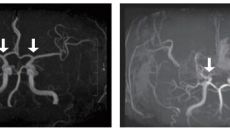

서울대병원, 전국 소아 모야모야병 장기 역학 분석 결과 발표

[이상섭 기자] [라포르시안] 희귀난치성 뇌혈관질환 '소아 모야모야병'의 발생 양상과 치료 및 예후를 전국 단위로 분석한 결과- 7시간전